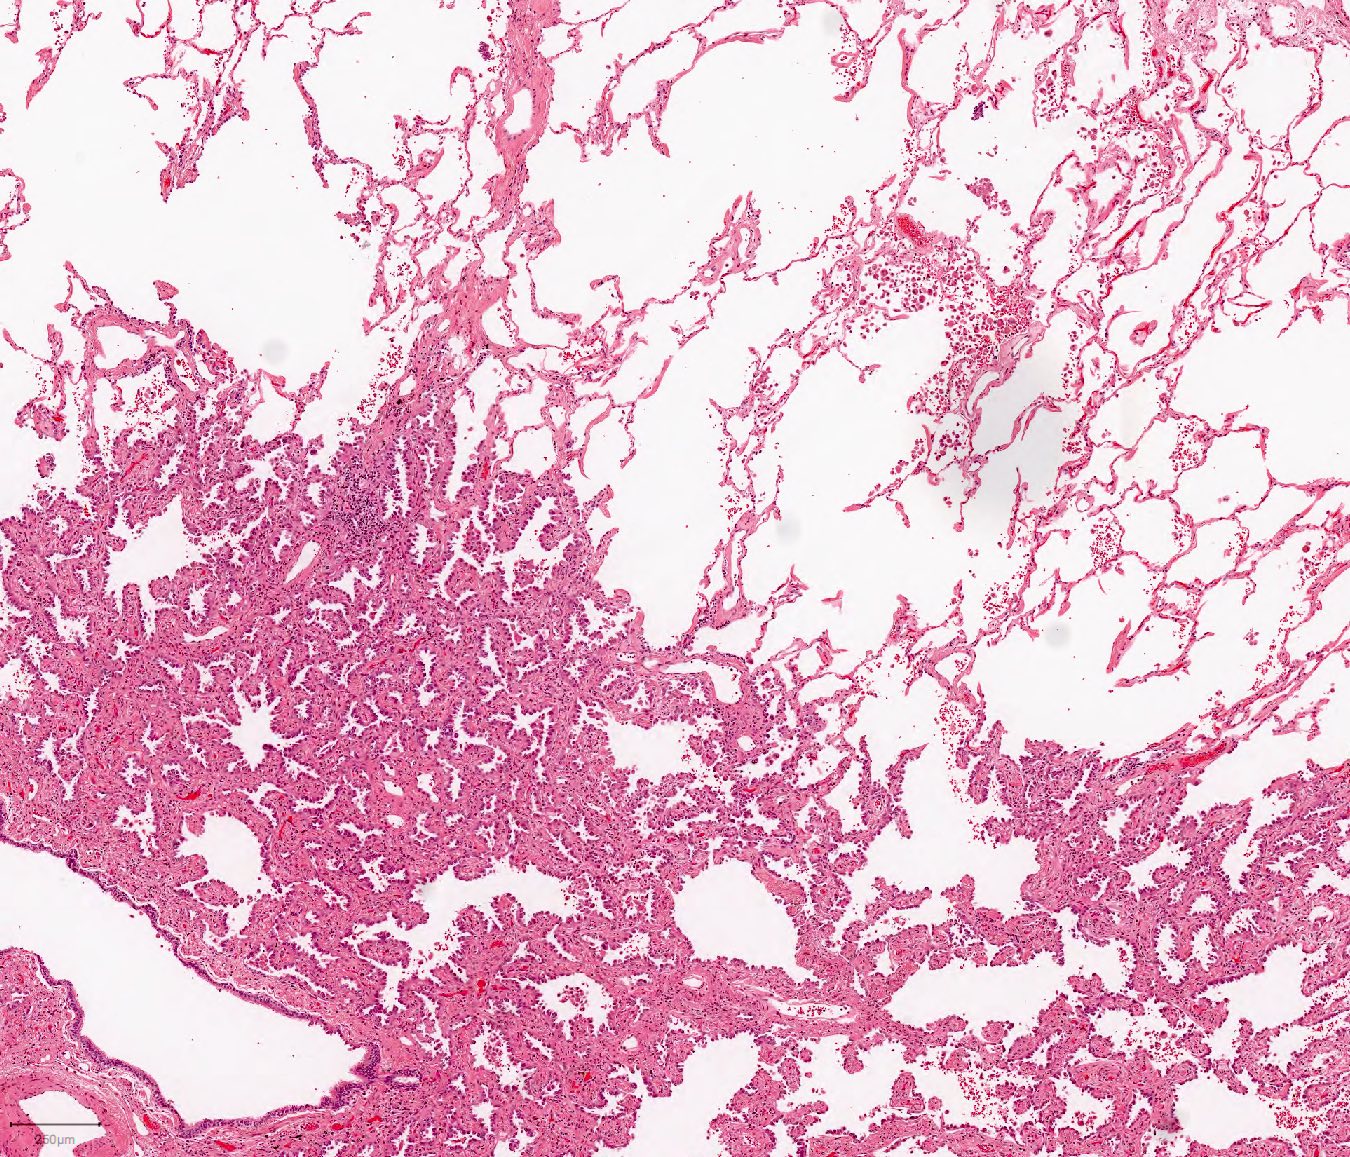

Lepidic Pattern Adenocarcinoma

Pulmonary adenocarcinoma with lepidic growth pattern BosnianPathology

Patterns of invasive adenocarcinoma. (a) Lepidic, this tumor shows a

Pathology Outlines Lepidic adenocarcinoma

Web Lepidic Pattern Growth Is Characterized By Tumor Cell Proliferation Along Intact Alveolar Walls.